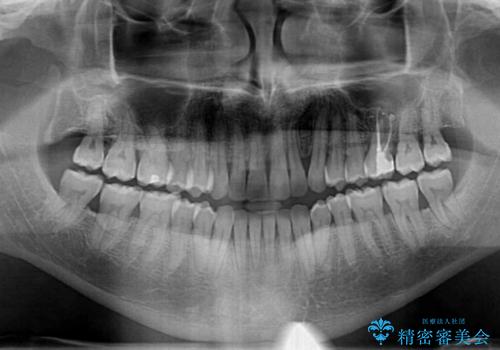

- 前歯でものを噛みきりたいとのことで来院された患者様です。

以前矯正治療を経験されたそうですが、舌の突出癖により上下前歯に隙間ができている様子でした。

前歯の非接触改善は、インビザラインの得意とするところですが、マウスピース矯正は絶対に継続できないとのことで、ワイヤー装置にて矯正治療を行うこととしました。

舌の突出癖が改善されない限り、非接触改善は見込めないため、トレーニングを徹底するように指示しました。

舌のトレーニング自体は簡単なものですが、無意識下でも舌が突出しないようにしなければならないため、毎日継続することが最大の難関です。

時間はかかりましたがトレーニングを頑張ってくださり、無事に前歯を接触させることができました。